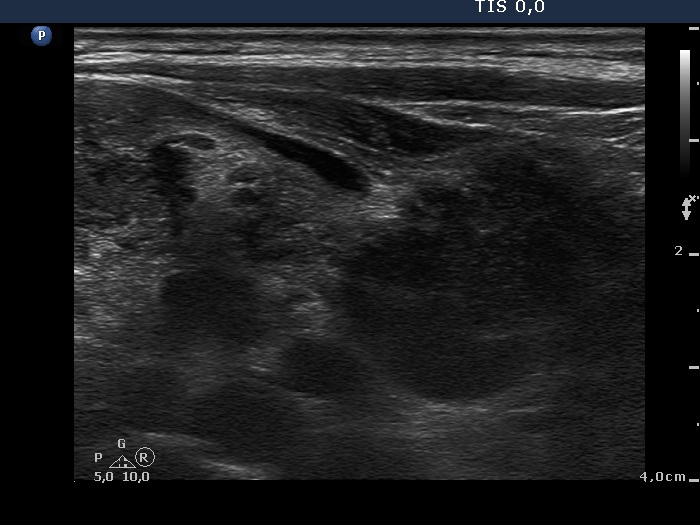

Lymph nodes - case 382 (ultrasonographic picture 16)

Left side of the neck lateral to the thyroid, another longitudinal scan.